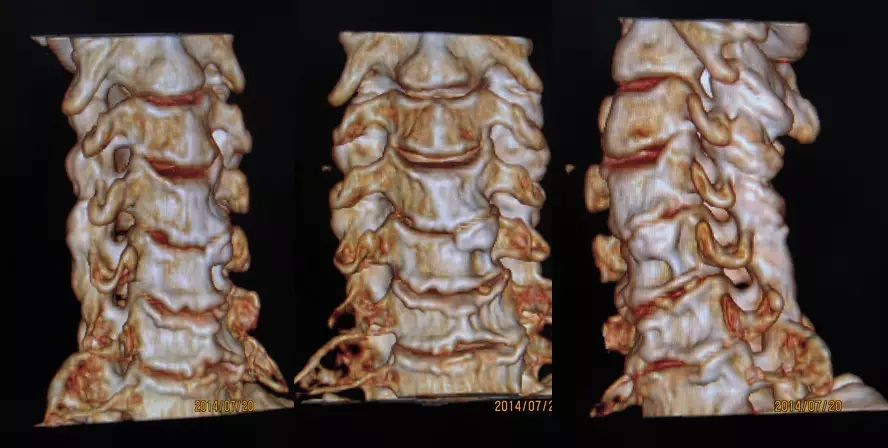

1.颈椎、腰椎骨质增生

骨质增生症多发于中年以上。一般认为由于中年以后体质虚弱及退行性变;长期站立或行走及长时间的持于某种姿势,由于肌肉的牵拉或撕脱、出血,血肿机化,形成刺状或唇样的骨质增生;骨刺对软组织产生机械性的刺激和外伤后软组织损伤、出血、肿胀而致。

颈椎4、5、6椎体最为常见

腰椎3、4、5椎体最为常见

构椎关节骨质增生

腰椎骨质增生VR像

颈椎骨质增生VR像

骨结构改变:多表现为椎体边缘部唇样骨增生、硬化。

退变引起的骨结构改变